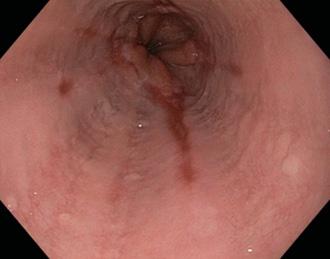

Dolor retroesternal (irradia a espalda y hombro izquierdo) típicamente agudo y pleurítico (hincada), que al sentarse e inclinarse hacia adelante y con el decúbito o inspiración.

En el examen físico, se advierte frote o roce pericárdico (forma seca); también se observa al signo de Ewart (matidez subescapular izquierdo por colapso alveolar a causa de un derrame pericárdico) en casos de pericarditis húmeda.

En el ECG, se establecen 4 fases:

I: Elevación del segmento ST de forma difusa (con la concavidad hacia arriba) , asociado a infradesnivel del PR (cambio + precoz)

II: A los 3-4 días, el segmento ST se vuelve isoeléctrico.

III: Posteriormente, onda T negativa y simétrica.

IV: Finalmente, hay un retorno a lo normal (en 2-3 meses).

En casos de derrame, hay alternancia del eje eléctrico.